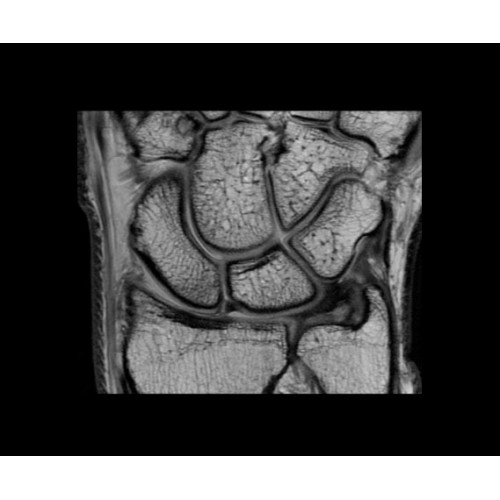

• OrthoWorks — программное решение для визуализации структур опорно-двигательного аппарата с прекрасным контрастированием тканей.

Поле обзора 50x50x50 см и апертура шириной 70 см позволят достоверно визуализировать сложные анатомические области для пациентов с крупным телосложением, например, плечи и бедра. Феноменальная однородность системы SIGNA Architect обеспечивает наиболее широкое поле обзора с улучшенными характеристиками градиентов. Ничто не останется незамеченным.